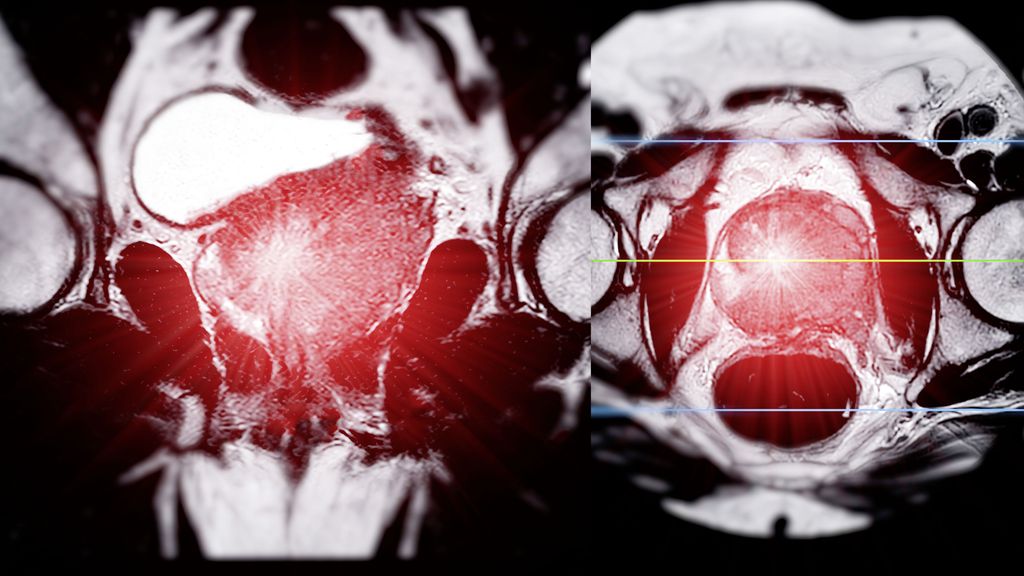

Wichtig zu beachten ist, dass in der EMBARK-Studie eine konventionelle und keine PSMA-basierte Bildgebung angewandt wurde. Wir wissen aus kürzlich publizierten Untersuchungen, dass in einer Population von Personen, die den EMBARK-Kriterien entsprachen, bei ca. 80% mit einer PSMA-PET-Bildgebung eine Rezidivlokalisation möglich ist:2

-

ca. 25% Lokalrezidiv

ca. 50% regionäre Lymphknotenmetastasen

ca. 25% weiter entfernte Lymphknotenmetastasen

ca. 25% Knochenmetastasen und Kombinationen davon